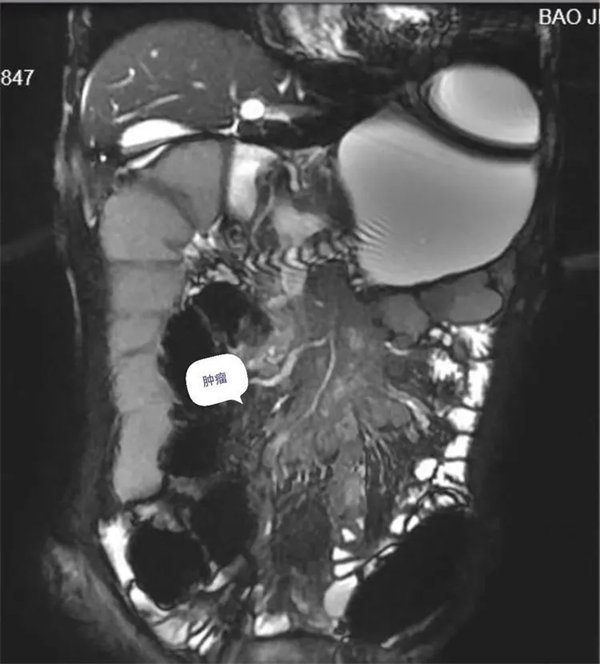

病例1:患者,老年男性,以腹痛腹脹不適就診,常規腹部CT,腸系膜血管CT成像,由于腸管堆積,內容物影響,病變與腸管密度差別不大,未發現明顯病變。經多學科會診商討后,建議行小腸磁共振成像(MRE)檢查,進一步查明病因。

圖1,胃,小腸,結腸充盈顯示良好,局部小腸壁增厚,腸系膜病變組織包繞腸系膜動脈及分支血管塑形生長呈等T1,等T2信號腫塊。

圖2,動脈期,病灶無明顯強化,邊緣輕度強化。

圖3:延遲期,顯示腸系膜根部病變逐漸輕度強化。胃,結腸充盈顯示良好,腸壁強化,未見異常。